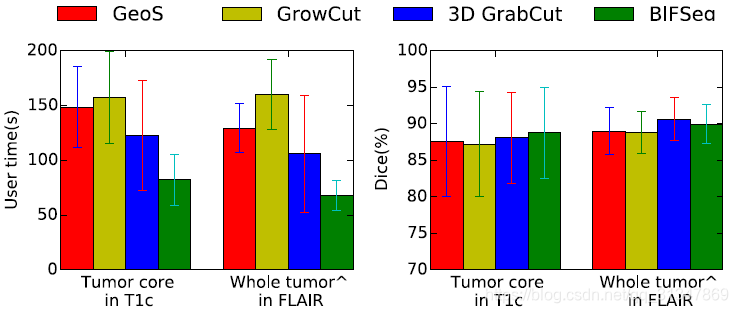

比较 BIFSeg 和 1)P-Net/PC-Net 的初始分割结果;2)用 CRF 处理之后的分割结果;3)BIFSeg(-w) 的分割结果(基于 Eq(1),所有像素的权重 w ( i ) = 1 w(i) = 1 w(i)=1),以及其他交互式分割方法:用于 2D 分割的 GrabCut,SlicSeg,Random Walks;用于 3D 分割的 GeoS,GrowCut,GrabCut 3D

BIFSeg 可以实现花费更少的用户时间,但精度上与其他方法相近或更高。

(4)与其他交互式分割方法的比较: